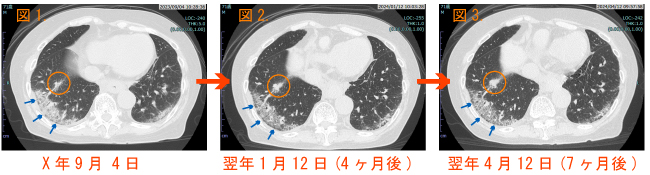

CT画像の所見と経過:(図1)青い矢印に示した右肺の一番下、背中側にすりガラス陰影が写っています。すりガラス陰影は第1に間質性肺炎という特殊な肺炎を疑う所見ですが、図1→図2→図3と7ヶ月の経過でほとんど変化がありません。一方で、そのすりガラス陰影の近傍にオレンジ色の◯で囲んだ部位に、内部が密に詰まった辺縁に小さなトゲがあるように見える小結節影(粒状の塊)があります。経過観察した過程で14mm(図1)→ 16mm(図2)→ 19mm(図3)と少しずつ増大しています。青い矢印のすりガラス陰影が間質性肺炎であれば、間質性肺炎を背景とする肺癌の併発することは一般的にもよく知られています。この結節影は肺癌を否定できないと考え総合病院の呼吸器外科へ紹介となりました。

KT4.jpg​​​​​​​